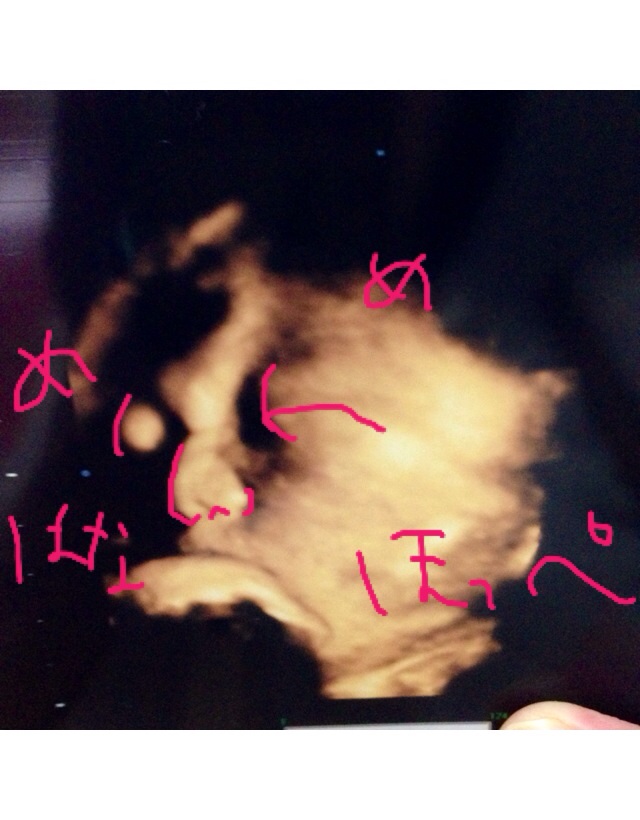

もう上手くエコーに映らなくなってきたよーーぶしゃいく。

推定3021g

あ、この産院には先生が3人いるのですが、前に聞いた先生じゃなかったから、また「うちの子、鼻 高いですよね!」って聞いちゃいました。←しつこい笑